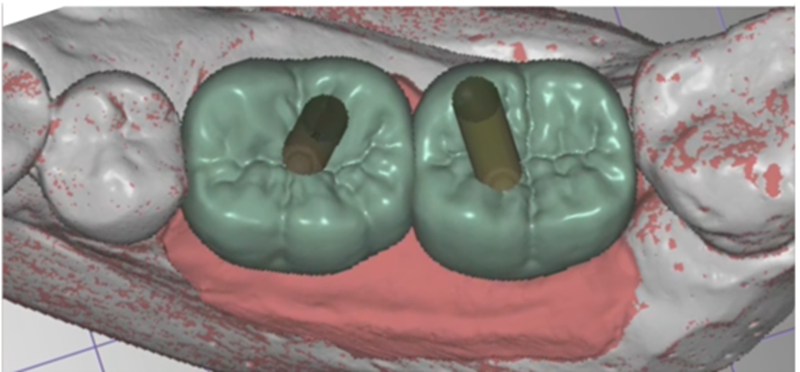

Selecionamos um caso clínico para ilustrar o fluxo de trabalho digital para Mini Cônico, onde foram planejadas duas coroas unidas nos elementos dentários 36 e 37 em zircônia monolítica, feitas sobre o pilar para próteses múltiplas.

Na etapa de escaneamento foi selecionado o transferente digital do Mini Cônico e optamos por trabalhar no fluxo e biblioteca do software Exocad (onde é realizado o design da prótese), o qual tem toda a linha de componentes da Implacil De Bortoli e de seus análogos digitais.

Neste caso, a prótese múltipla foi desenhada sobre o Mini Cônico e as duas coroas foram fresadas unidas. Após a maquiagem final da zircônia monolítica, as coroas foram parafusadas sobre o Mini Cônico com um torque de 10 Ncm.

Podemos acompanhar o passo a passo das etapas, desde a seleção da altura do transmucoso do Mini Cônico até a instalação das coroas unidas no fluxo totalmente digital sem a utilização de componentes metálicos.